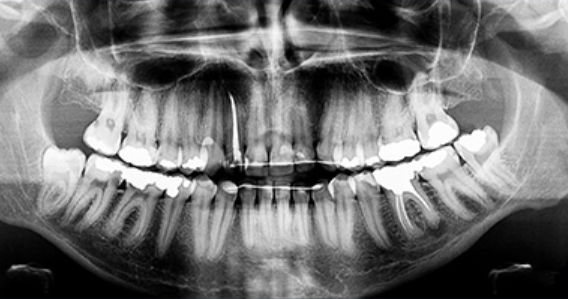

매복된 사랑니는 3D 첨단 CT촬영으로 상태를 정밀검사하고 발치계획을 세웁니다.

다양한 상태의 사랑니들을 다루어본 경험이 풍부하기 때문에 잇몸 속에

매복되어 보이지 않는 사랑니 발치가 가능합니다.

최첨단 3차원 CT를 이용하여 사랑니 뿌리의 위치와

신경관 위치 등을 정밀하게 분석한 후 시행하고 있습니다.